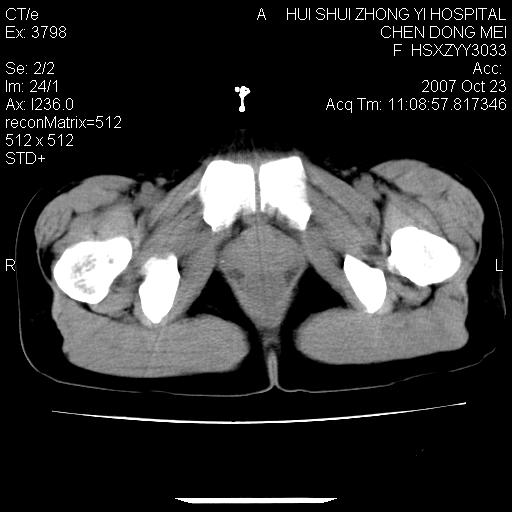

标题: CT10156:女.43岁,发现中下腹部包都块2年 [打印本页]

标题: CT10156:女.43岁,发现中下腹部包都块2年

发现中下腹部包都块2年。2年来月经不规律。

腹腔及盆腔恶性肿瘤可能性大,腹膜后可见肿大的淋巴结影,恶性畸胎瘤?

腹腔巨大软组织密度影,边缘光滑,包膜完整,内囊变坏死。腹膜后及盆腔内淋巴结肿大。结合病史考虑卵巢癌可能性大。

病灶内可见脂肪密度影,考虑畸胎瘤可能性大

病变巨大,呈囊实性改变,包膜较厚且完整,内见分膈,周围脏器明显受压移位,病变与左侧附件关系密切,考虑来源左侧附件的囊腺瘤,不除外癌变可能;畸胎瘤可能性较小。

病变巨大,呈囊实性改变,包膜较厚且完整,内见分膈,周围脏器明显受压移位,病变与左侧附件关系密切,考虑来源左侧附件的囊腺瘤,盆腔内见肿大淋巴结,不除外癌变可能。